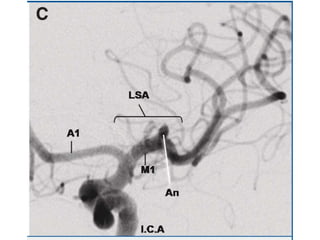

Perforating branches

• Lenticulostraite arteries - branches of MCA that

enter anterior perforating substance (APS)

• origin from superior or posterosuperior MCA

• 3 groups : medial, intermediate and lateral

• MEDIAL: least constant, 1-5 branches from M1, enter

medial APS

• INTERMEDIATE: constant, few branches dividing,

atleast 1 major artery

• LATERAL: constant S shaped course, enter

posterolateral part of APS

Perforating branches • Lenticulostraitearteries - branches of MCA that enter anterior perforating substance (APS) • origin from superior or posterosuperior MCA • 3 groups : medial, intermediate and lateral • MEDIAL: least constant, 1-5 branches from M1, enter medial APS • INTERMEDIATE: constant, few branches dividing, atleast 1 major artery • LATERAL: constant S shaped course, enter posterolateral part of APS

Angiographic Sylvian Point (ASP)

• It is the most medial point where the last

cortical MCA branch (usually the angular

artery) turns inferiorly to exit the sylvian

fissure.(On AP view)

• This point approximates the apex of the insula

and represents the posterior limit of the

lateral cerebral sulcus.

Angiographic Sylvian Point(ASP) • It is the most medial point where the last cortical MCA branch (usually the angular artery) turns inferiorly to exit the sylvian fissure.(On AP view) • This point approximates the apex of the insula and represents the posterior limit of the lateral cerebral sulcus.